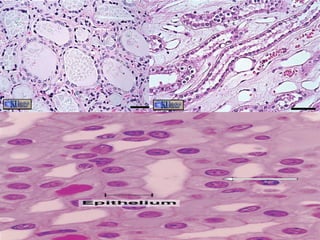

Simple Cuboidal Epithelium Structure Single layer of cube shaped cells Function Secretion and transportation in glands, filtration in kidneys Location Glands and ducts (pancreas & salivary), kidney tubules, covers ovaries

Simple Columnar Epithelium Structure Elongated layer of cells with nuclei at same level Function Absorption, Protection & Secretion When open to body cavities – called mucous membranes Special Features Microvill i , bumpy extension of apical surface, increase surface area and absorption rate. Goblet cells , single cell glands, produce protective mucus. Location Linings of entire digestive tract

Transitional Epithelium  Structure Many layers Very specialized – cells at base are cuboidal or columnar, at surface will vary. Change between stratified & simple as tissue is stretched out. Function Allows stretching (change size) Location Urinary bladder, ureters & urethra

Simple Cuboidal EpitheliumStructure Single layer of cube shaped cells Function Secretion and transportation in glands, filtration in kidneys Location Glands and ducts (pancreas & salivary), kidney tubules, covers ovaries

Simple Columnar EpitheliumStructure Elongated layer of cells with nuclei at same level Function Absorption, Protection & Secretion When open to body cavities – called mucous membranes Special Features Microvill i , bumpy extension of apical surface, increase surface area and absorption rate. Goblet cells , single cell glands, produce protective mucus. Location Linings of entire digestive tract